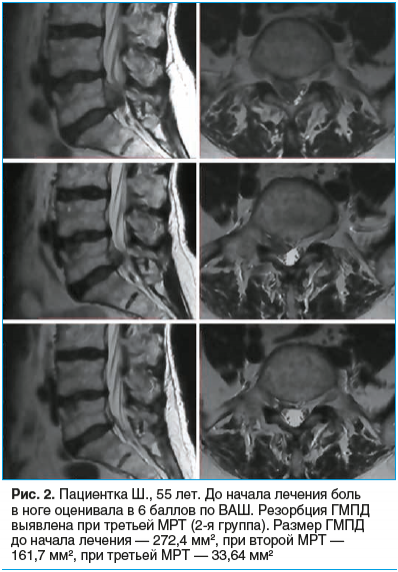

Резорбция грыжи что это такое